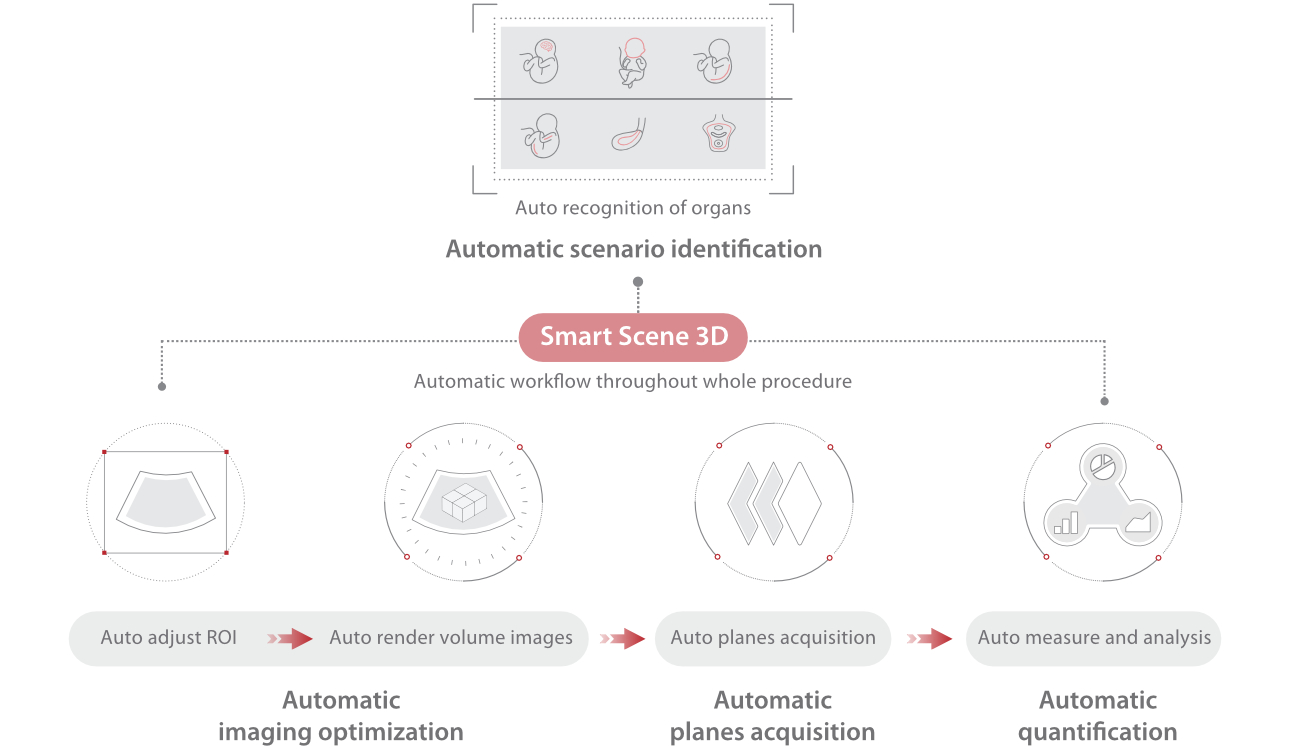

Nuewa I9? ??? ???? ?? ??? ?? ??? ???? ?? ??? ???? ???? ??? ?????. ??? ??? ??? ?? ????? ?? ???? ???? ???? ???? ??? ???? ??? ??? ???? ??? ???? ??? ?? ?????.